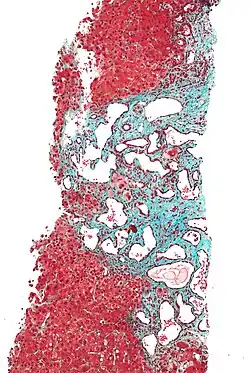

Low magnification micrograph of a bile duct hamartoma. Trichrome stain.